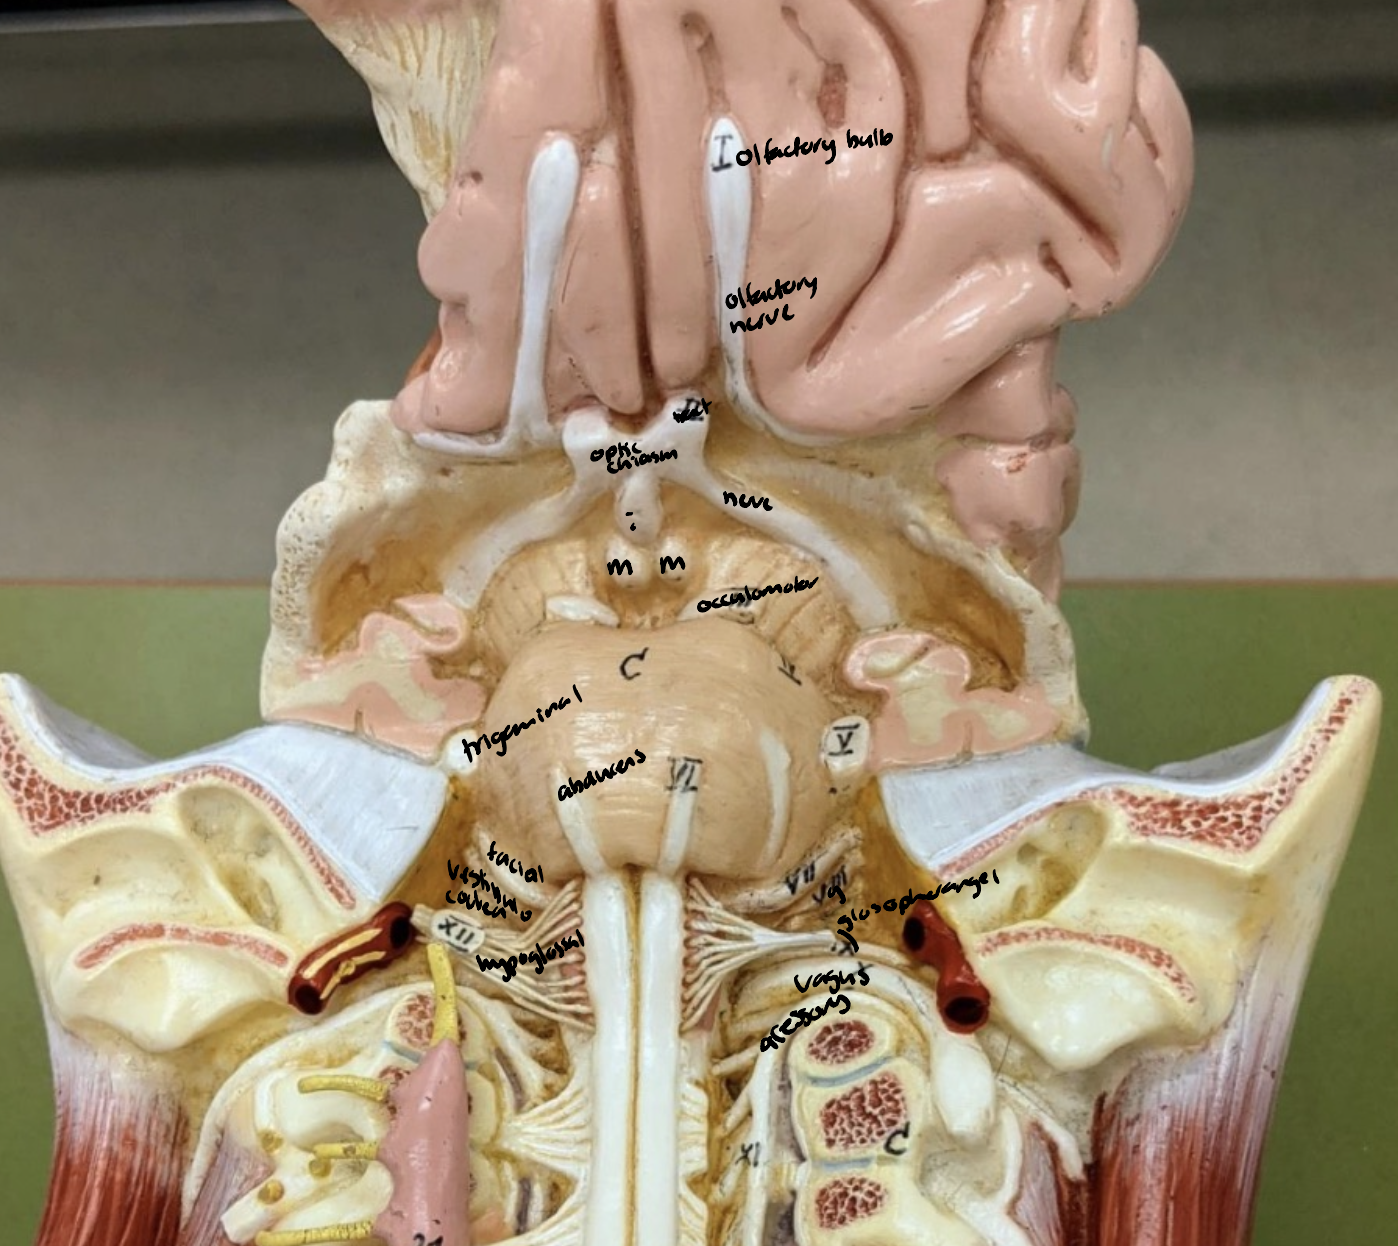

Pathway of CNI

Cranial Nerves